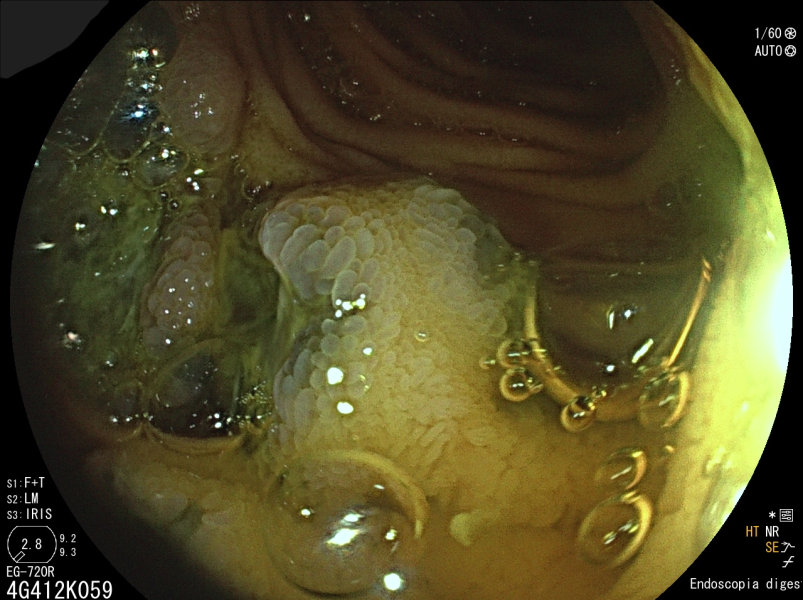

[MENÇÃO HONROSA] Intraductal papillary mucinous neoplasms - Perioral pancreatoscopy as a potential weapon in optimising the surgical approach!

Fotografia